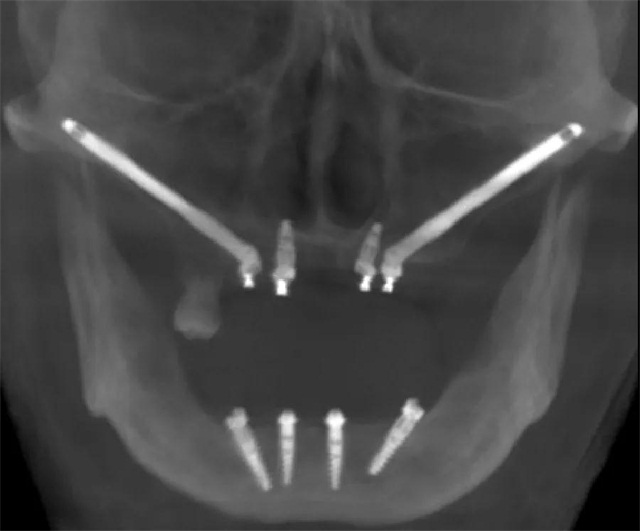

面对上颌骨骨量严重不足的情况下,颧骨种植成上颌骨严重萎缩患者种牙新选择。他介绍,多颗牙或全口牙种植与建设桥梁相似,桥墩越稳越牢固,桥墩的位置要选在承受力强的地方才可靠。牙弓就像一个弧形的桥,在满足修复为前提的条件下,面部的任何有骨的部位都可以作为“桥墩”基地来考虑种植,对于上颌骨极端骨缺失的患者,想要术后即刻修复,可以考虑把植体往前外上方放在面部的颧骨上,往后放在上颌骨后面的蝶骨翼板上,这些地方都是面部非常结实的“桥墩”,把萎缩牙槽骨需要的支撑力量引到面部这些有良好骨质的部位,有点类似生活中斜拉桥,有效避开没有骨质的上颌窦区,这样萎缩的牙槽骨就有希望即刻种植、即刻修复。经过最近几年大量的穿翼种植,熊靖宇院长逐渐发现了规律,即“熊氏三角规律”。

最后熊靖宇院长进行了总结,严重萎缩的上颌骨可以选择穿颧种植和穿翼板种植,能达到即刻负重的结果,从而消除了骨移植的依赖,极大的改善患者对固定咬合的需求,拓展了口腔种植的范畴。